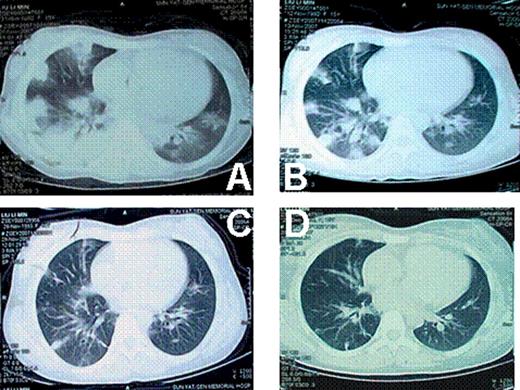

At the onset of the pulmonary diseases, anti-GVHD drugs (Including prednisone, CsA) were already withdrawn for both cases. There was no GVHD progression after withdrawal of the anti-GVHD drugs. Both cases had fever, ranging from 38 to 39 centigrade. Patients were short of breath. Oxygen inhalation was needed. Case 1 was in severe hypoxia. The oxygen saturation was down to 70%∼80% at the peak severity. Neither of the 2 cases was in need of mechanical ventilation. CT images showed that these 2 cases had similar lung injuries (Fig 1 and Fig 2). Tissue biopsy revealed that different pathogens were involved in these 2 cases, although they had identical disease history, similar duration after transplantation, same clinical symptoms and signs, even similar CT images. The histological findings of lung biopsies showed that the pathogen for case 1 was aspergillums, whereas that of case 2 was tubercle bacillus. Both cases responded well to the specific treatment, respectively. Patients are now in disease-free state.

Both tuberculosis and fungus infection could show diffused foci on CT image. The diffused lesions of tuberculosis tend to fuse, whereas little cavities were more frequently seen in fungus infections. After treatment, the lesions of fungus were much easier to be clear than tuberculosis. Diagnostic treatment might be used to distinguish these 2 diseases if biopsy cannot be performed or pathogen culture is negative.

lung CT of case 1. A: when the pulmonary infection began; B: 2 weeks later; C: 5 weeks later; D: 7 weeks later.